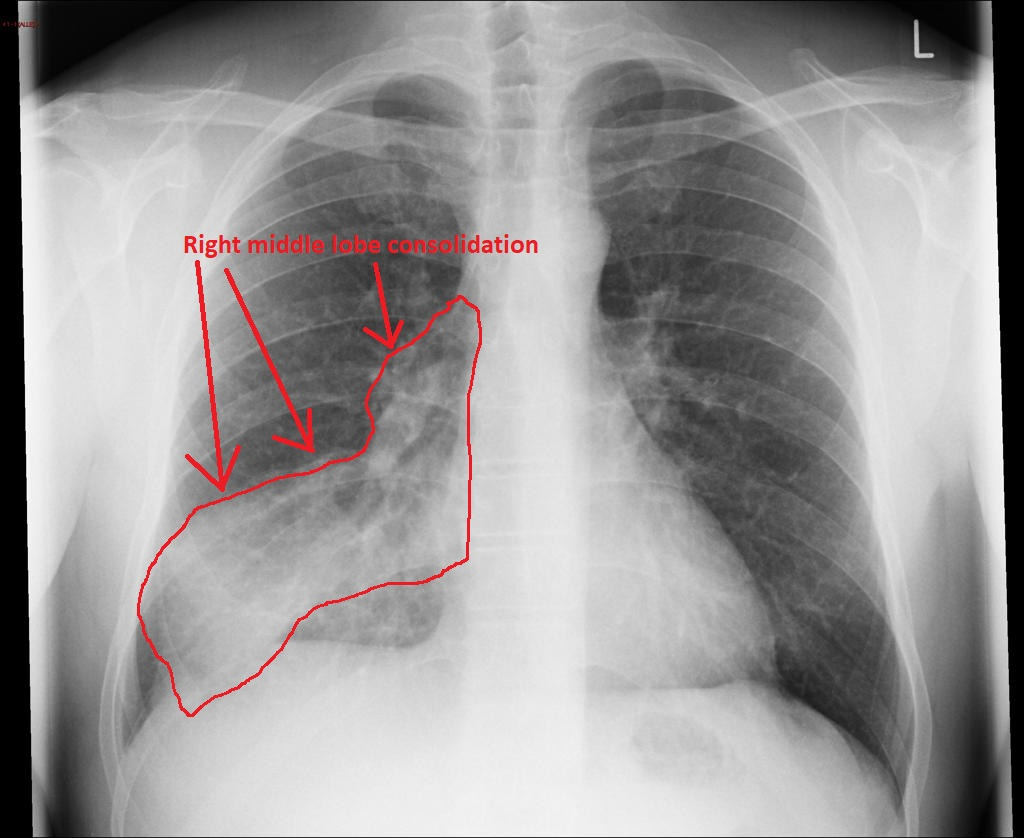

Aspiration pneumonia를 CT에서 감별할 때 가장 중요한 개념은

dependent distribution이다.

이는 중력 방향으로 폐 병변이 분포한다는 의미이다.

CT에서 aspiration pneumonia의 전형적인 모습은 patchy consolidation이다.

폐의 특정 폐엽이 완전히 하얗게 차기보다는

불규칙한 음영 증가가 여러 군데 나타나는 경우가 많다.

또한 air bronchogram이 동반될 수 있다.

영상에서 aspiration pneumonia를 atelectasis와 구분하는 것은 매우 중요하다.

두 질환 모두 폐의 posterior lower lung에 음영 증가가 나타날 수 있기 때문이다.